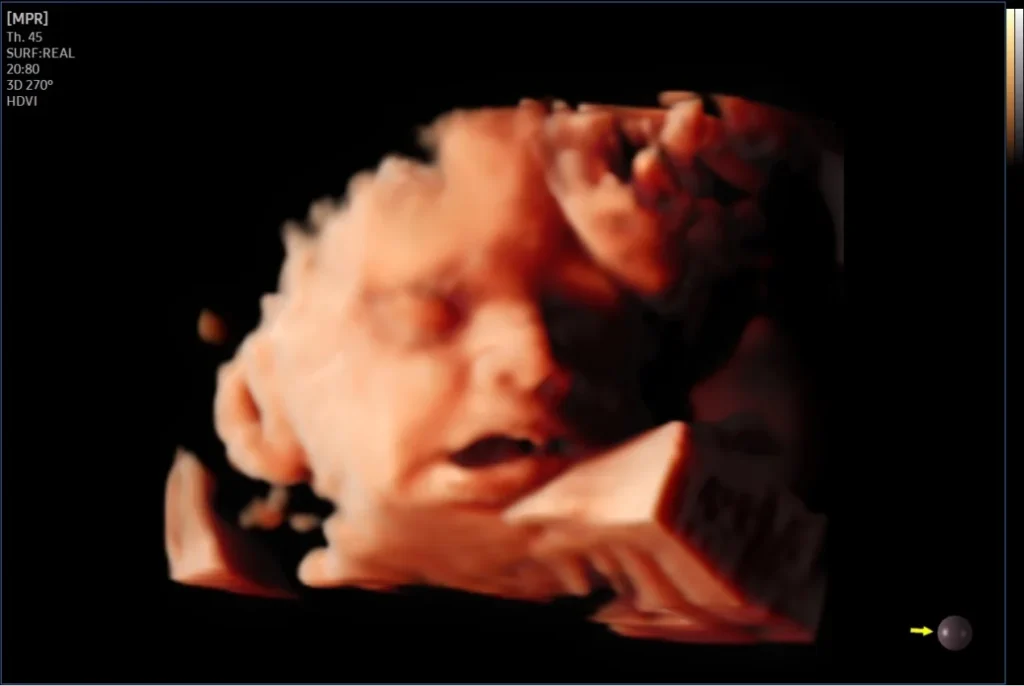

3D/4D Fetal / Obstetric Ultrasound

High-definition 3D Fetal images for better anatomical assessment and parental bonding.